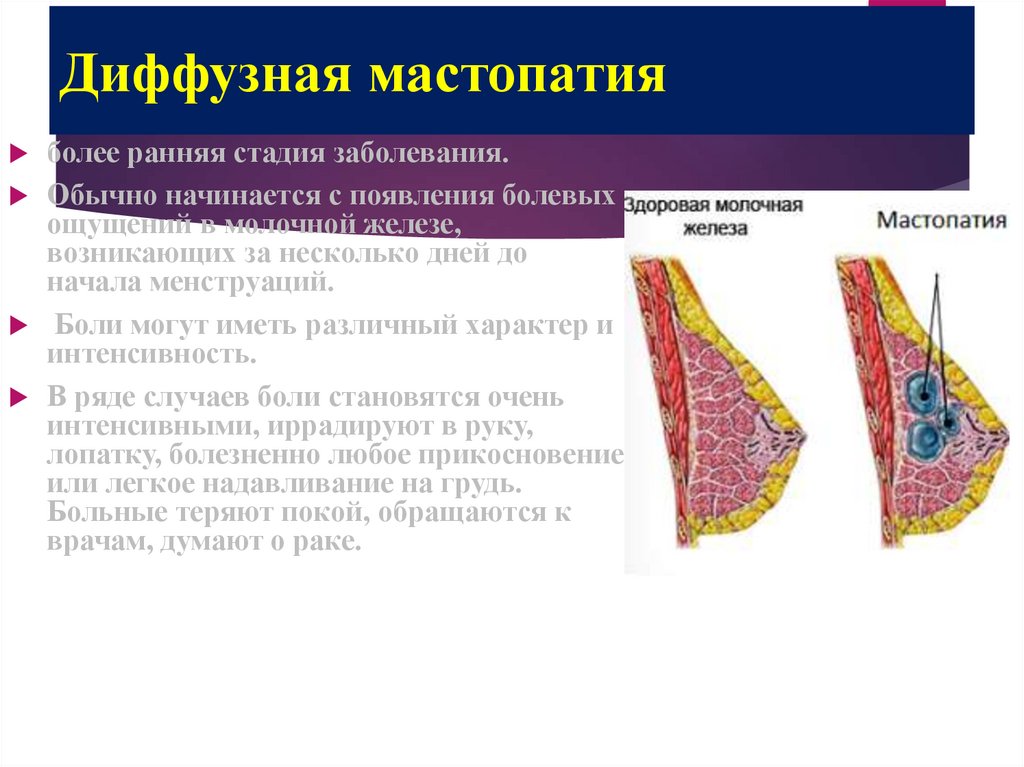

Уплотнения в груди могут быть вызваны различными причинами, включая кисты, фиброаденомы или инфекционные процессы. Важно понимать, как правильно подходить к их лечению и когда обращаться к врачу. Следующие советы помогут вам разобраться в этом вопросе и обеспечить здоровье своей груди.